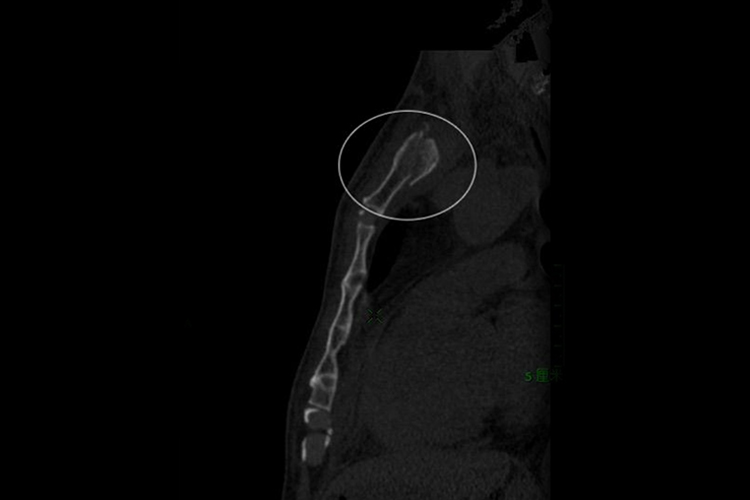

胸骨柄骨折进行CT检查的影像结果提示,局部骨皮质不连续,患者可出现胸骨部位疼痛,以及活动受限等症状。

胸骨柄位于胸骨上部,骨折进行CT检查的影像结果提示胸骨柄骨皮质不连续,还可见双侧胸腔少量积液,触诊骨折部位明显压痛。当累及多根肋骨骨折时,产生胸廓反常呼吸运动,影响呼吸、循环功能等。